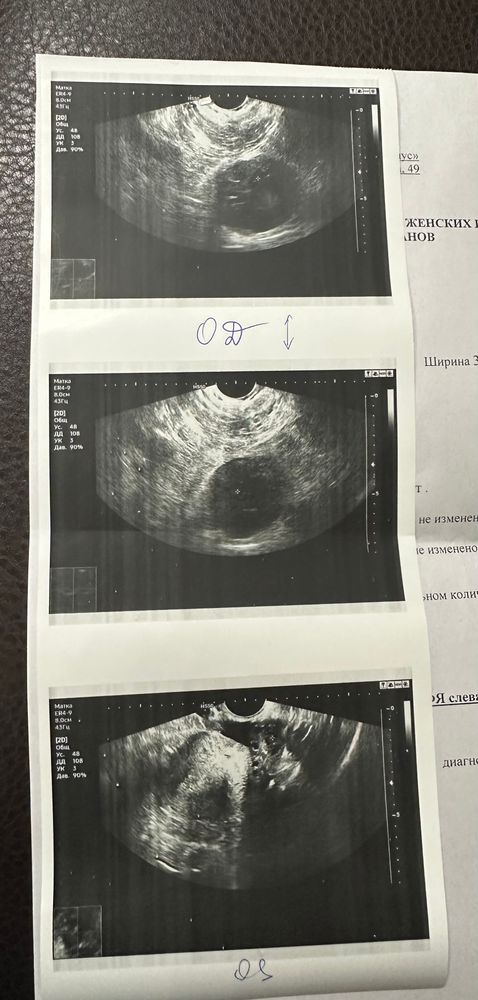

Посмотрите узи, вопрос пол желтое тело.

Девочки, здравствуйте, сходила на узи. До месячных 6 дней. Цикл обычно 33дня. Овуляция на 18-20 день. Странно, что узист не написал про желтое тело,, но сказал , что овуляция была в правом яичнике. Он прям здоровый по фоткам.

Якобы там же есть фоликул с неровными контурами 6 мм похож на жт , но не факт, что это оно. Жидкость позади матки есть в небольшом количестве, что так же говорит о свершившейся овуляции.

Судя по размерам жёлтого тела (а это жёлтое тело) то скоро пойдут месячные. УЗИ у вас хорошее.

Анастасия, я уже год на Актиферт гино , то же самое что дифертон. Дюфастон без надобности сказала врач. До этого жт всегда визуализировалось и было примерно 12-15 мм. Я сегодня сходила к другому узисту, он гинеколог со стажем, но на узи выучился несколько лет назад. Вот думаю может перепутал что то. Как так жт нет или оно маленькое при том , что яичник большой.

Счастливая дважды мама, жт маленькое потому, что оно уже угасает и то, что контуры у него не ровные это норма и я бы не сказала, что он большой, если в сравнении с левым то да, больше. Вы бы посмотрели, что в сравнении с вашими другими УЗИ на размеры. Может это ваша физиологическая особенность.

Если жт 6 мм, то оно угасающее. Слишком маленький размер для нормального жёлтого тела